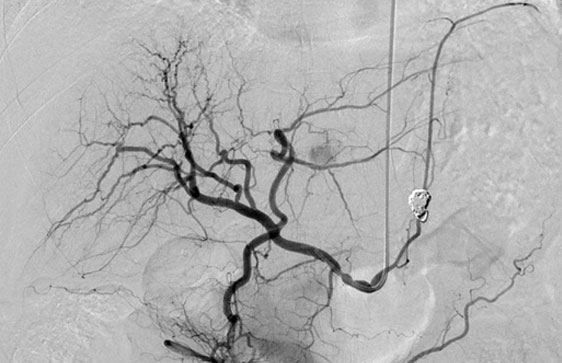

血管造影検査とは

血管造影検査とは、血管の状態や血液の流れを調べるために造影剤を用いてカテーテルという管を脚や腕の血管から目的の場所まで進め、狭くなった血管を拡げたり、出血した血管をつめて止血したり、腫瘤の栄養動脈を閉塞させ、がんを死滅させたりと様々な方法で治療をおこないます。血管造影検査は外科的手術をおこなわず、できるだけ体に傷を残さずに病気を治療する方法です。

当院の血管造影検査

2017年1月の血管造影装置更新に伴い、検査室を改装し、より患者さんにリラックスして検査を受けていただけるようなデザインを採用しました。検査室内のディスプレイも56インチ大型液晶ディスプレイを採用しており、より多彩な画像情報を術者やスタッフに提供できるようになりました。